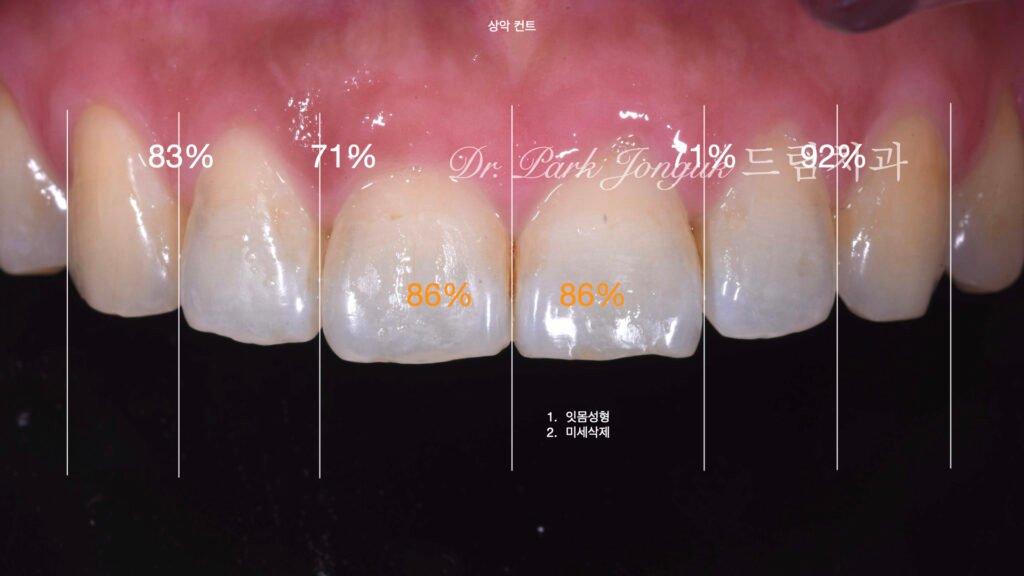

2. 임상 상태 진단 및 문제점 분석 (사진 1)

2.1 초진 소견 (Initial Assessment)

[사진 1 참조] 환자분은 교정 완료 후 다음과 같은 고민으로 내원하셨습니다.

- 치축의 부조화: 전치부 끝부분이 소량 순측으로 뻐드러져 보임.

- 색조 불만족: 변색된 치질로 인해 전체적인 미소의 명도가 낮음.

- IPR 후유증: 치아 사이사이가 시각적으로 꽉 막혀 있어 입체감이 결여됨.

2.2 심미적 역학 분석

치아 교정 시 공간 확보를 위해 시행하는 스트리핑은 치아의 인접면을 직선적으로 만듭니다. 이를 그대로 방치한 채 라미네이트를 부착하면 치아가 수평적으로 비대해 보이고, 소위 ‘풍선처럼 부푼(Bulky)’ 형태가 되어 인위적인 느낌을 주게 됩니다.